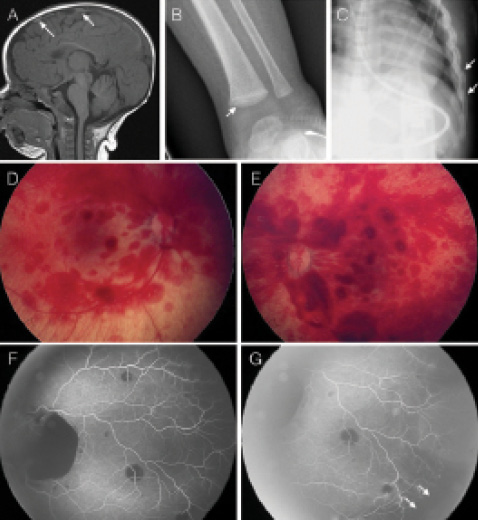

Abusive head trauma (AHT), frequently termed shaken baby syndrome, refers to a constellation of clinical findings—classically the triad of subdural hemorrhage (Figure 1A), bilateral retinal hemorrhages, and anoxic encephalopathy—from which clinicians infer physical child abuse. Classic metaphyseal fractures of long bones (Figure 1B) and rib fractures (Figure 1C), especially when they are in different stages of healing, and skin ecchymoses are other clinical findings suggestive of inflicted trauma.

Figure 1. Radiographic features of AHT: subdural hemorrhage (A, arrows), classic metaphyseal lesion (B, arrow), and lateral rib fractures (C, arrows). Fundus photos of a 12-week-old girl demonstrating retinal hemorrhages in multiple layers (D, E); notice the white centers. Fluorescein angiography findings in AHT (F-G). Blockage of background fluorescence from sub-ILM and subretinal hemorrhages. Peripheral retinal nonperfusion is present (arrows).

The most common retinal manifestation of AHT is multiple retinal hemorrhages in multiple layers of the retina, seen in approximately 85% of cases. Sub–internal limiting membrane (sub-ILM), nerve fiber layer, intraretinal, and subretinal hemorrhages are seen frequently in different stages of healing, often with white centers (Figure 1D and E), which constitute fibrin aggregations.6 Retinal hemorrhages are frequently bilateral, although unilateral involvement does not rule out a diagnosis of AHT.7 Sub-ILM hemorrhages can break through into the posterior hyaloidal space or vitreous cavity, resulting in vitreous hemorrhage. Macular retinoschisis, often caused by intraretinal blood dissecting the outer nuclear layer from the inner retina, has been demonstrated with optical coherence tomography (OCT) and postmortem histopathologic analysis of victims of AHT.8 Retinal tears, retinal detachment, and (rarely) pigment epithelial detachments have been reported.9,10 Furthermore, the presence of circumferential retinal folds surrounding the macula has been regarded as a specific sign for AHT and has been associated with fatal outcomes.11,12 Optic disc hemorrhages and papilledema as a result of increased intracranial pressure may also be observed.

Retinal neovascularization in response to peripheral retinal ischemia and nonperfusion has been identified as an important late clinical manifestation in infants with AHT, and this underlines the importance of evaluating these patients using widefield fluorescein angiography (Figure 1F and G).16-18 The mechanism behind the peripheral nonperfusion is not well understood. It is believed that several factors are involved, including venous stasis, direct vitreous shearing of the capillary network, and autonomic dysregulation of the retinal vascular network secondary to brain hypoxia and damage.18